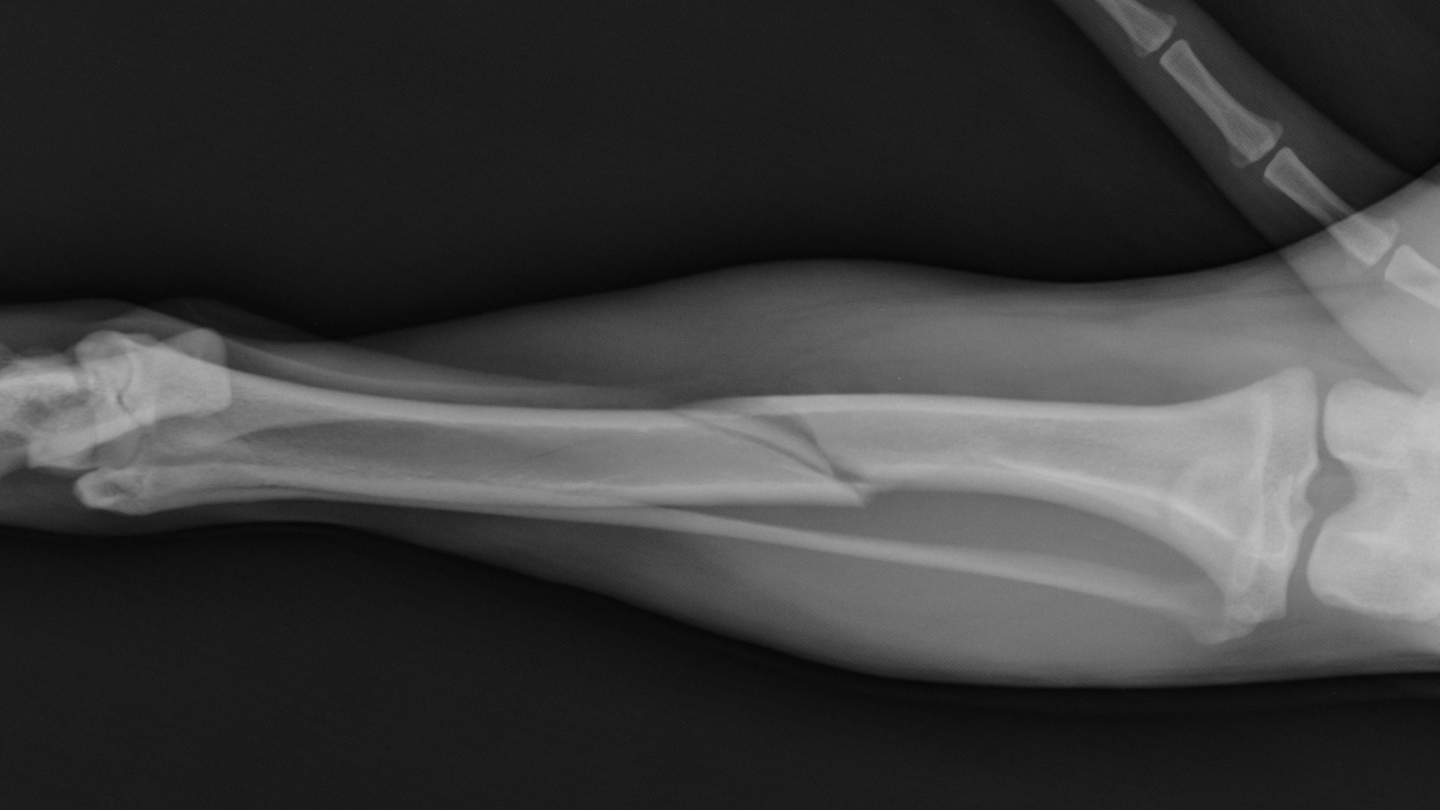

Thời gian liền xương trung bình cho gãy xương ống chân dao động từ 12 - 24 tuần (khoảng 3 - 6 tháng). Tuy nhiên, cần phân biệt rõ giữa liền xương trên phim X-quang (xương đã nối liền cơ bản) và phục hồi chức năng hoàn toàn (có thể đi lại bình thường, chịu lực đầy đủ). Liền xương trên X-quang thường xảy ra sau 4 - 6 tháng, nhưng để vận động tự nhiên mà không đau hay hạn chế, có thể mất thêm vài tháng nữa, thậm chí lên đến 1 năm ở một số trường hợp nặng.

Sau giai đoạn viêm, mô sẹo mềm được hình thành từ mô liên kết và sụn, giúp nối liền tạm thời hai đầu xương gãy và làm ổ gãy ổn định hơn. Theo thời gian, mô sẹo này dần khoáng hóa và chuyển thành mô xương non. Trên X-quang, dấu hiệu liền xương ban đầu thường thấy sau khoảng 4 - 6 tuần, với hình ảnh cầu xương bắt đầu xuất hiện.